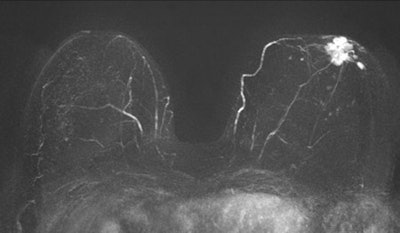

Kuhl and colleagues investigated whether a streamlined protocol, consisting only of the first postcontrast subtracted images and their maximum intensity projection (MIP) reconstructions, would be suitable for screening purposes. The idea was to trade some of the high sensitivity of breast MRI for acquisition and interpretation speed, with a long-term goal of increasing access to breast MRI by reducing the cost associated with the examination, according to Kuhl.

Kuhl and colleagues tested the protocol in a population of 443 women at increased risk of breast cancer who had undergone 606 breast MRI screening studies. Images were read by experienced breast radiologists who were asked to first review the MIPs and search for significant enhancement, and then to evaluate the first postcontrast subtracted images for any further categorization. (The first postcontrast subtracted images show the change in image due to contrast; MIP is a volume rendering method for 3D data.)

Kuhl's team found that the average time required to read MIPs was 2.8 seconds, while 28 seconds were required for the postcontrast subtracted images. Patient setup consumed the rest of the time required for the three-minute protocol. A total of 11 breast cancers were diagnosed, for an additional yield of 18.2 cancers per 1,000 women.

Of these cancers, four were ductal carcinoma in situ (DCIS) and seven were invasive, with a median size of 8 mm. All were intermediate or high grade. The streamlined protocol detected nine (82%) of the 11 cancers; specificity of the protocol was the same as that of the full protocol, at 94.4%. The streamlined protocol had 33 false-positive diagnoses, versus 35 for the full procedure.